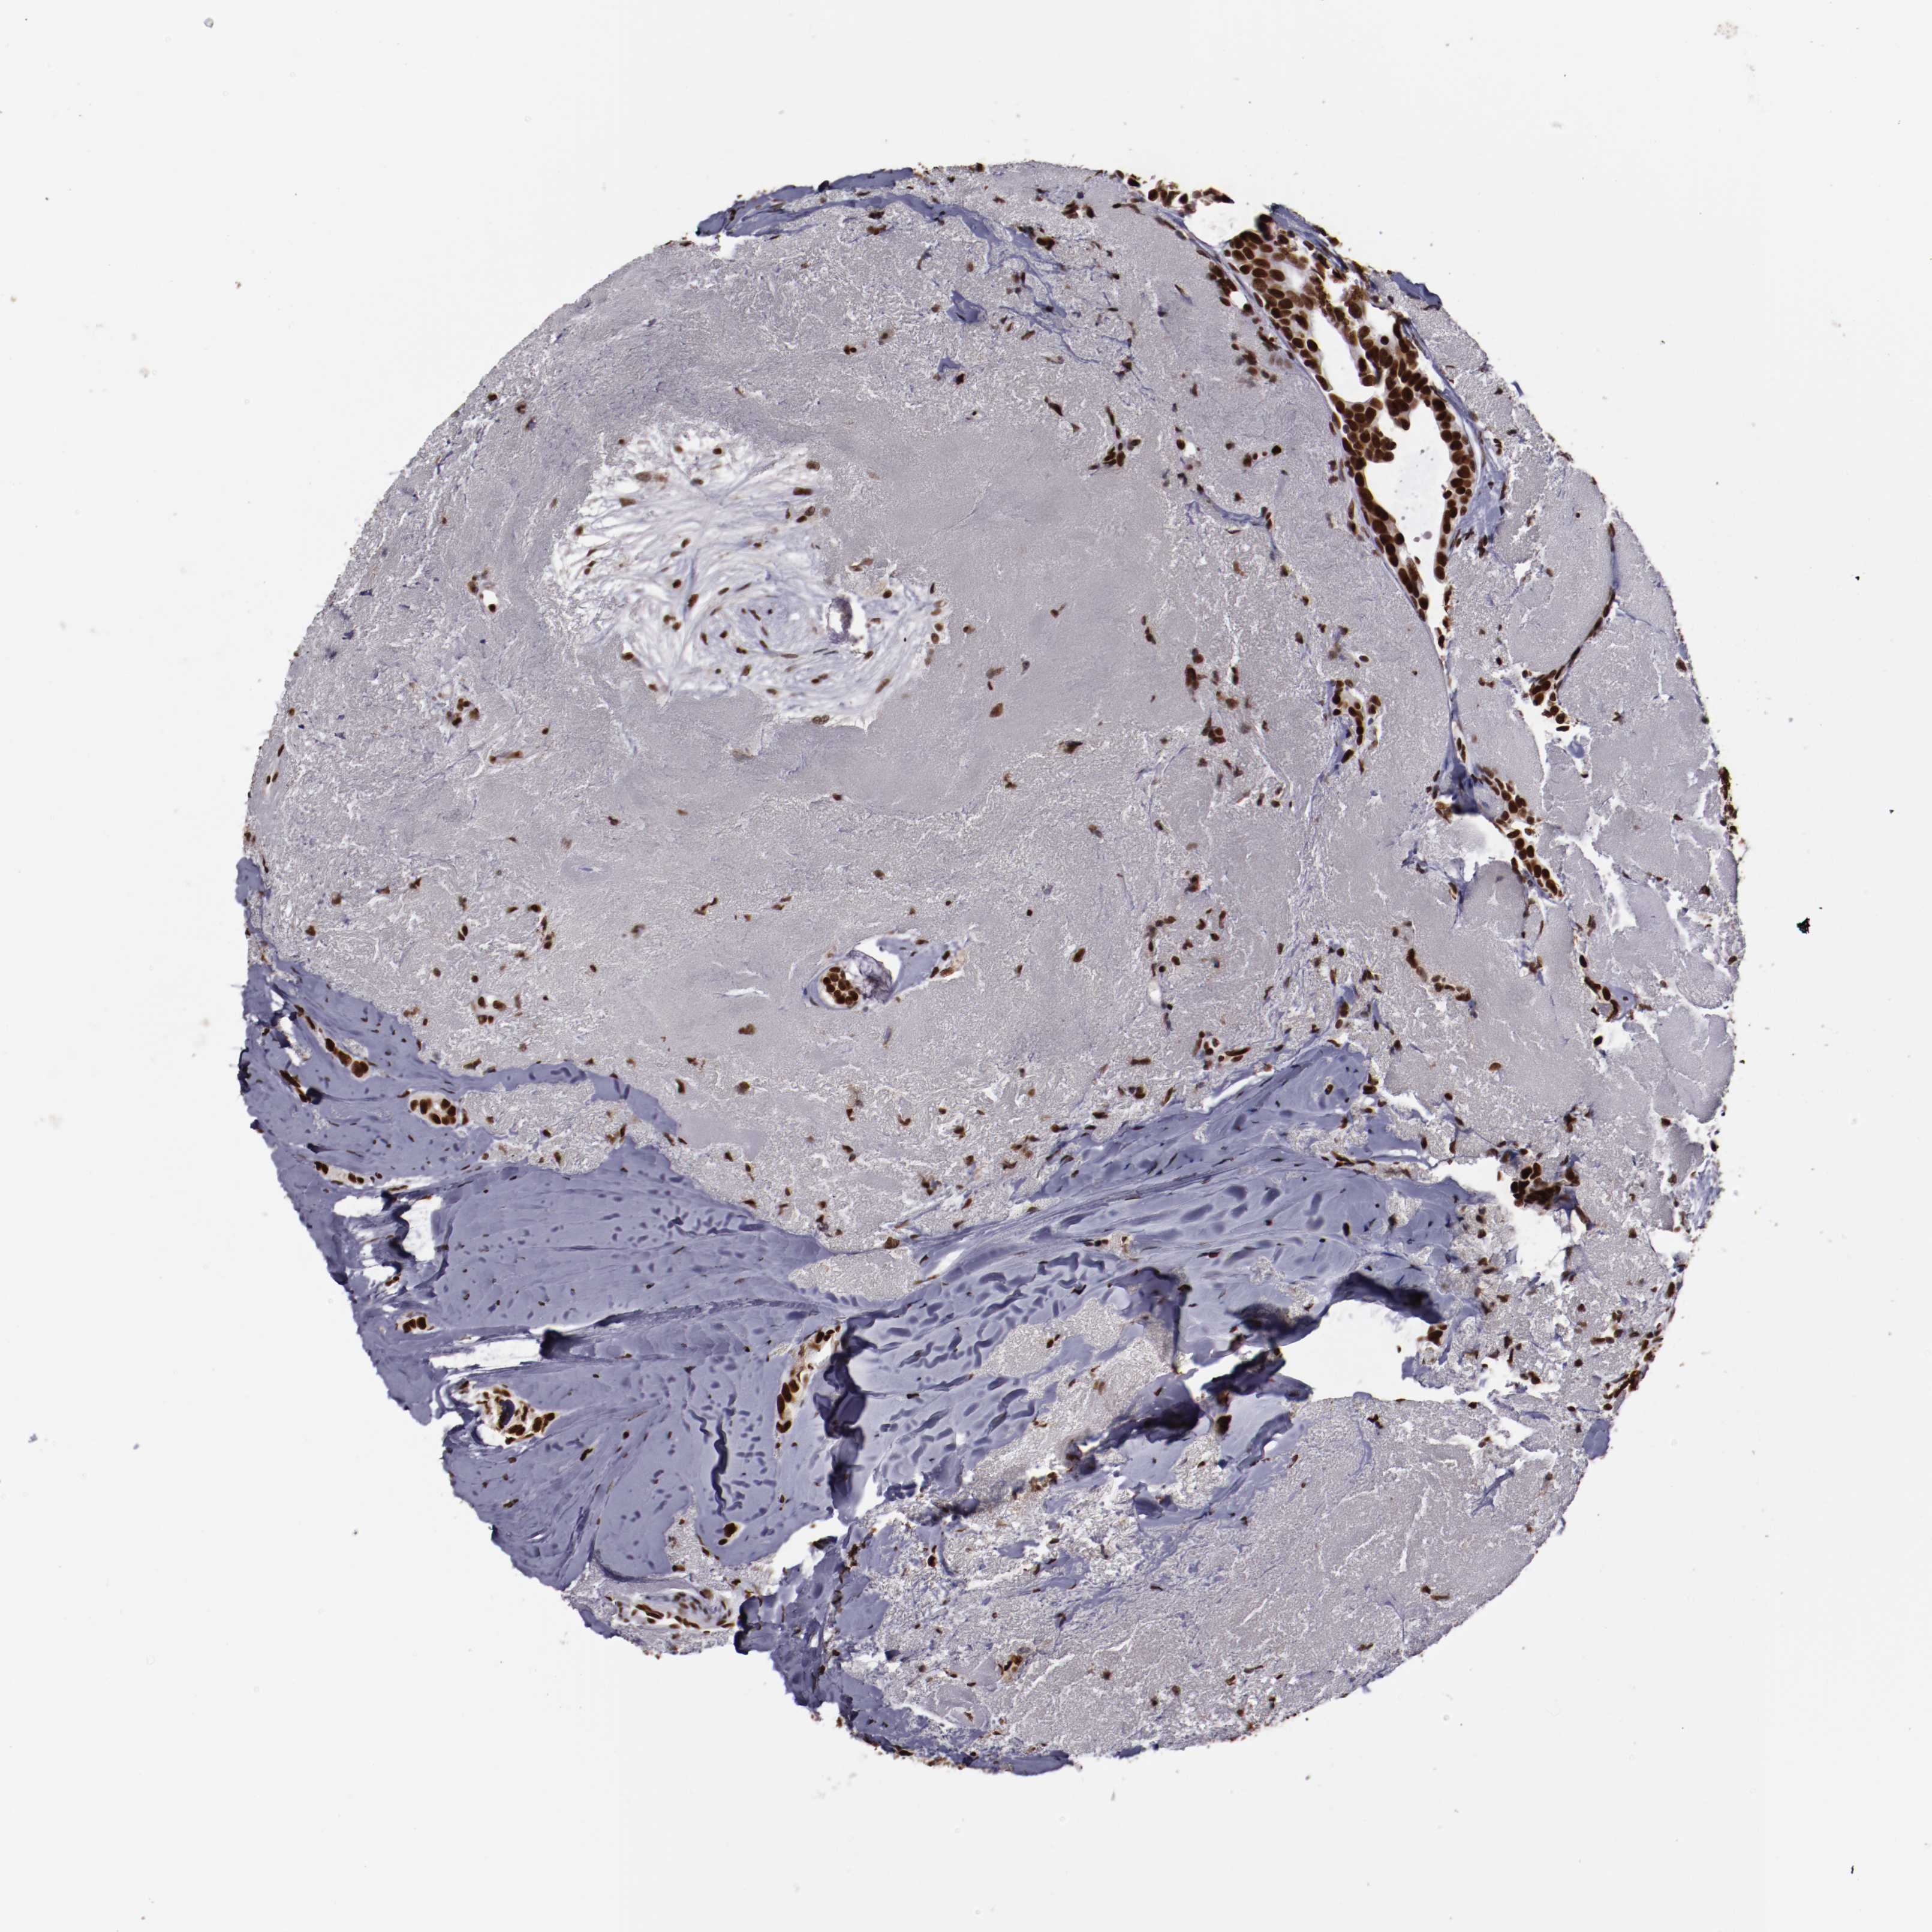

CANCER BREAST CANCER Show tissue menu

BRCA TCGA BRCA VALIDATION PROTEIN EXPRESSION

Breast cancer

Human cancer